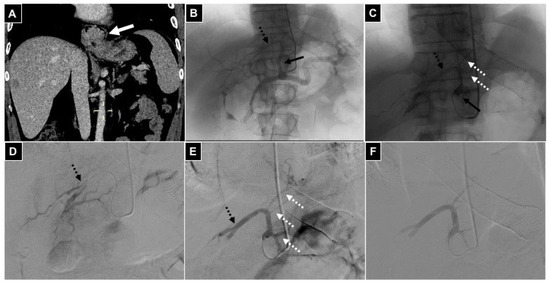

| 2 TAE | Gastric cancer | 2 Left hepatic a. | Left gastric a. | Bland microparticles |